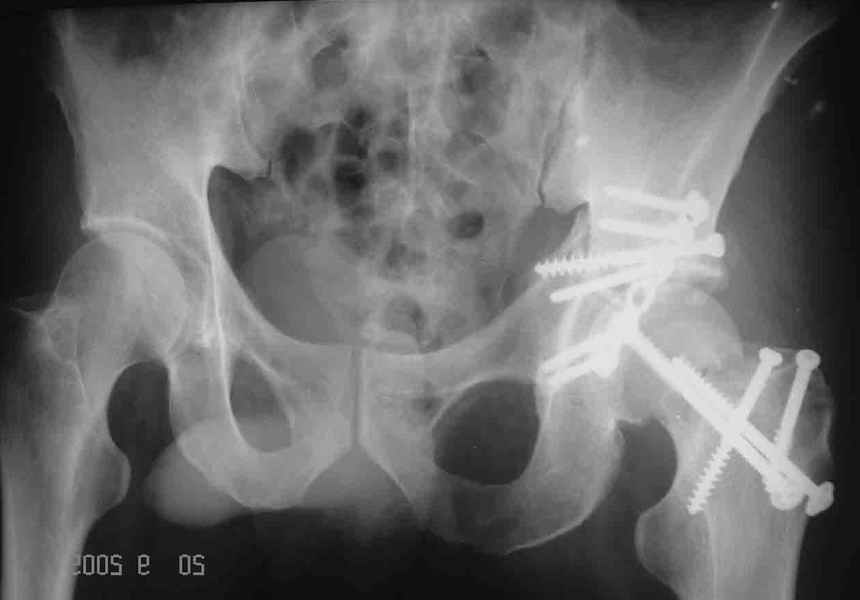

Уважаемые коллеги. Больной был оперирован в одну сессию 25 августа. Сначала на голень наложен спице-стержнвой аппарат. Затем выполнен остеосинтез вертлужной впадины Y-образным доступом. Пришлось дополнительно отсекать вертел. Шейка синтезирована спонгиозными винтами и спицами, вертел - спицами и стягивающей петлей. После операции находился на вытяжении 3 нед. Раны зажили первичным натяжением. Сейчас уже дома. Будет и дальше без нагрузки на левую ногу. Будем наблюдать в динамике. Ждем комментарии.

Наконец добрался до компьютера, прочитал коментарии, хочу внести дополнения к сообщенному.

Перелом шейки был многооскольчатйй очень медиальный, по сути шейку и вертел расколотило об подвздошную кость с кучей мелких фрагментов, вертел был полностьб вовлечен в перелом, головка заподлицо скрывалась в расширенной вертлужной впадине. Качество кости приличное. Остатки дуги Адамса с предварительно проведенными винтами я вколотил в головку и компрессировал винтами - оказалось прочно, но образовался дефект верхнего отдела шейки, который был заплнен фрагментами фиксироваными трансфрактурными спицами - отсюда пучек.

Вертел во время доступа пришлось еще рубить, т.к.

переломы распространялись чересчур дистально.

Отсюда еще пучек спиц.